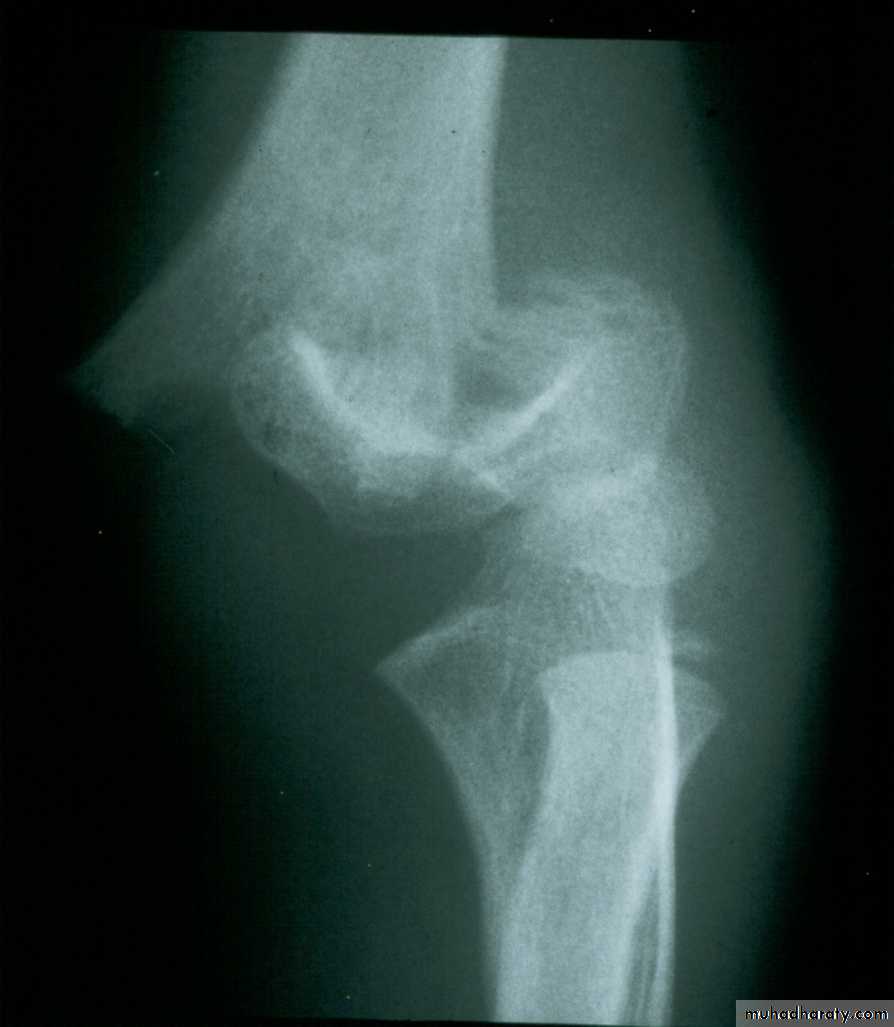

This classical Type III pattern

is obviously a flexion injury.With these one needs to be

prepared to do an open reduction !!

8 y.o.

Is this a simple extension

type supracondylar fracture ??

It also has

anterolatateraldisplacement !!

The distal fragment is

not flexed,but also it is not extended to any degree.

This also is a Type III Flexion Pattern.

What is differentabout this fracture?

But, if not recognized as such, it may be a problem.

This fracture was irreducible,

and required an open reduction !!!